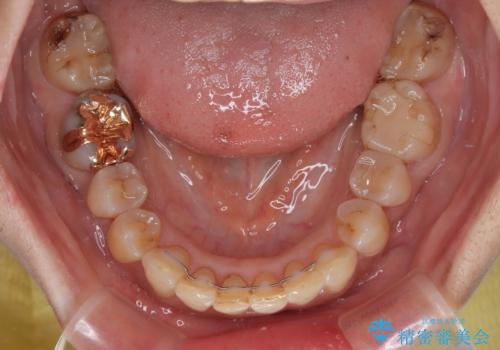

ディープバイトと前歯のデコボコ インビザラインによる矯正治療

- 前歯のディープバイトと叢生を気にして来院された患者様です。

目立ちにくい装置を希望されていたため、ワイヤー装置とインビザラインを提案したところ、インビザラインを希望されました。

下顎大臼歯が手前に倒れていたため、起き上がらせることで咬み合わせ高さを挙上し、ディープバイトと叢生を改善することとしました。